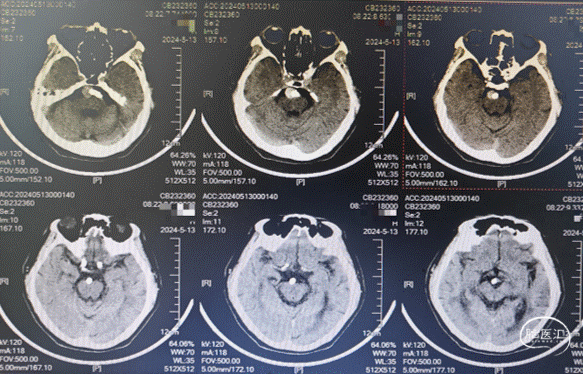

现病史:患者缘于入院3天前无明显诱因下出现头痛,搏动性头痛,无发热,无视物旋转,无恶心,无肢体抽搐等,就诊于合肥市第一人民医院行头颅CT平扫示:“基底动脉局部结节样影,动脉瘤?颅内多发腔隙性脑梗死”。患者及家属为求进一步治疗就诊我科,拟“基底动脉动脉瘤”收住。病程中,患者神志清楚,精神一般。

基底动脉局部呈瘤样扩张,瘤颈约13.66mm,最大截面大小约13.8mm*13.7mm,瘤内密度不均;左侧椎动脉V4多发钙斑附壁,相应管腔轻度狭窄;左侧颈内动脉虹吸部见钙斑附壁,相应管腔轻中度狭窄,最窄处位于C6,狭窄率约68%;左侧颈总动脉及颈内动脉C1近段见混斑附壁,相应管腔轻度狭窄,最窄处狭窄率约24%;主动脉见钙斑及混斑附壁,相应管腔轻度狭窄。